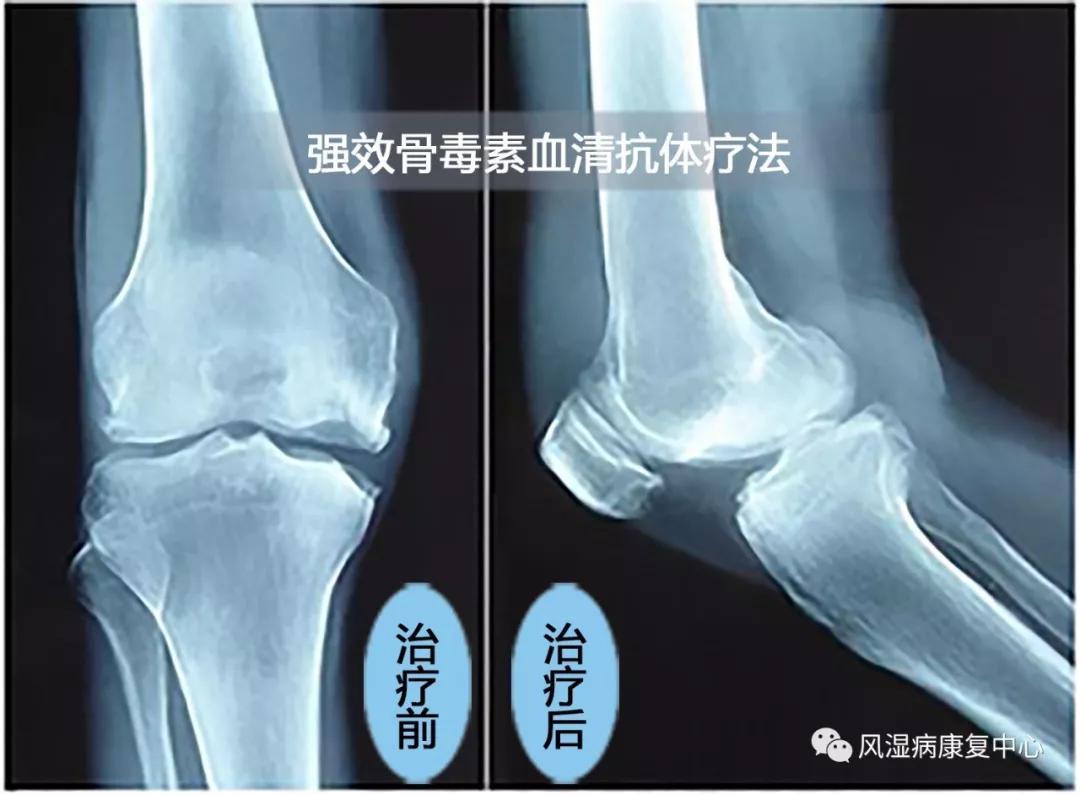

济南博爱风湿病医院,针对骨关节疼痛采用血清抗体疗法,清除体内炎性致病菌,平衡体内免疫,从根源上解决风湿病、关节炎,多年来为无数患者解除了病痛,久负盛誉。

医院独家引进美国“强效骨毒素血清抗体”疗法,治疗各种急性和慢性顽固性疼痛,时间短、见效快,治疗效果显著,深受患者好评。